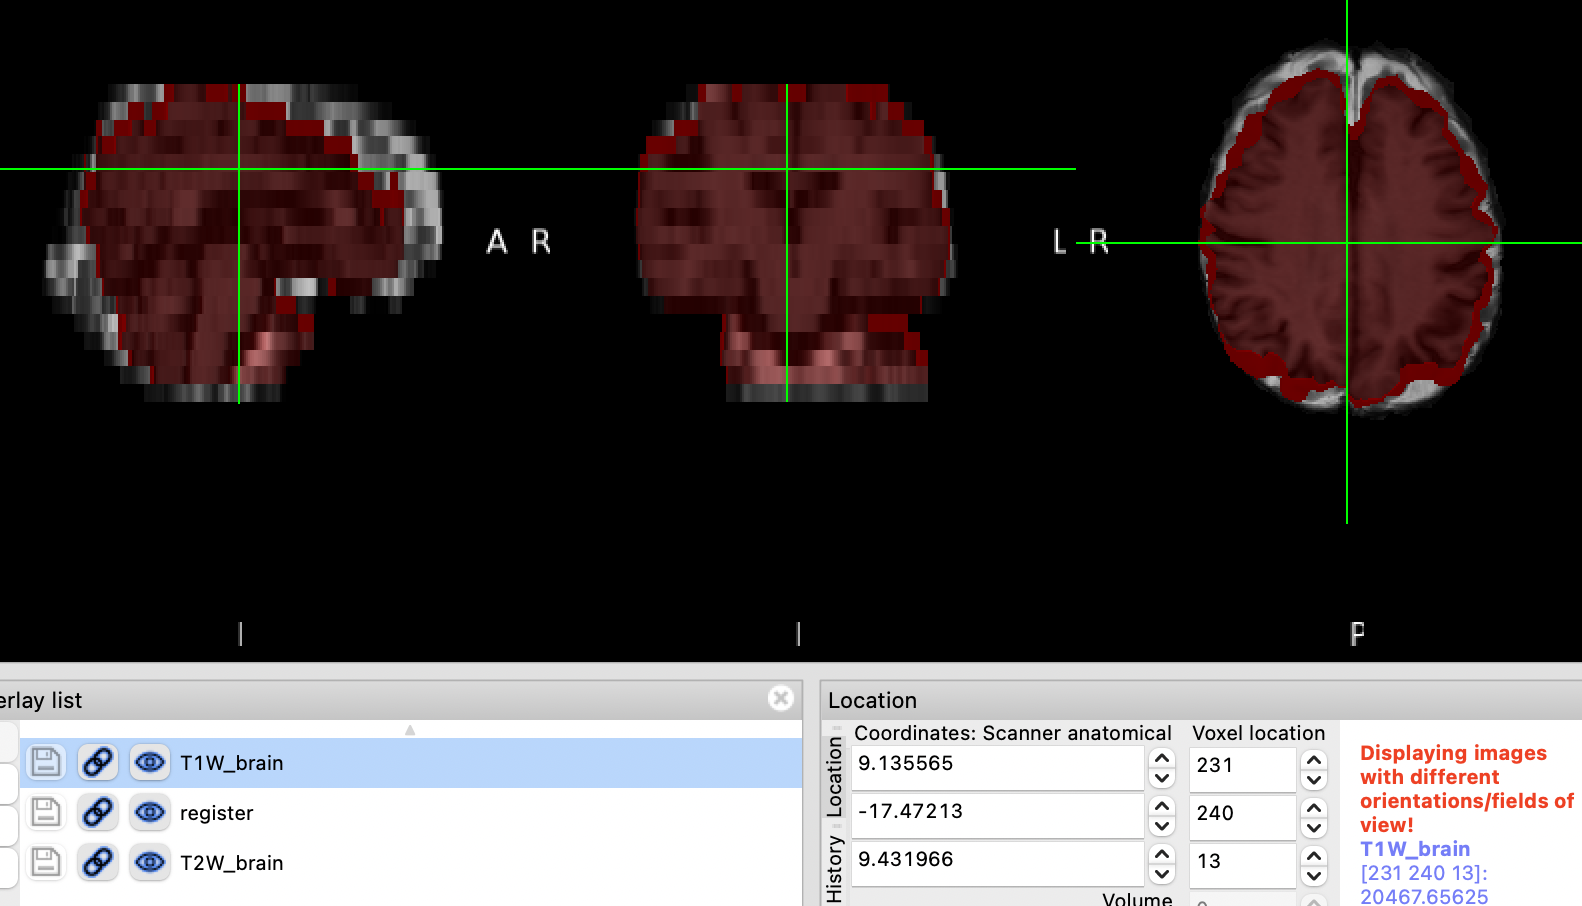

红色是配准后的T1w,和T2w还是没有对的很齐